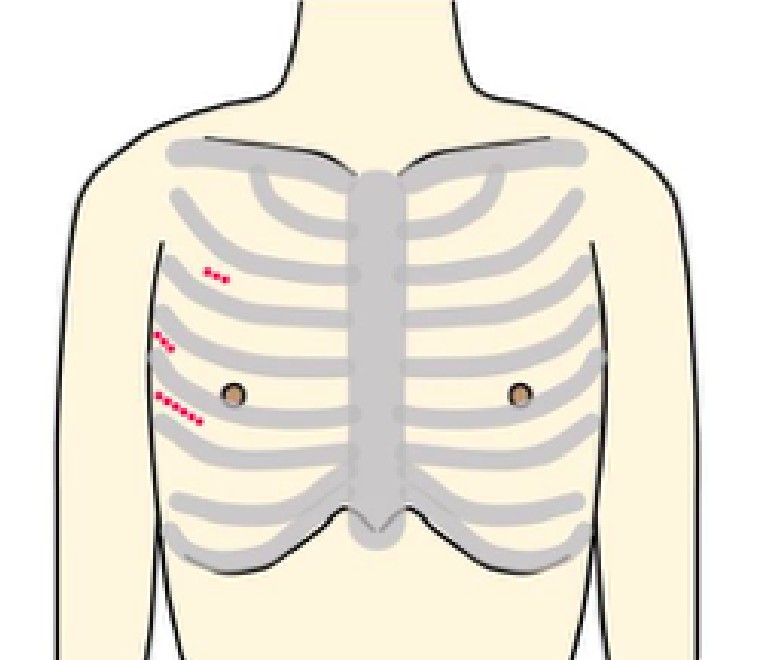

Minimally Invasive Cardiac Surgeryの略で、心臓低侵襲手術のことを意味します。

従来であれば胸骨という胸の真ん中を約20cm程切開しますが、MICSでは肋骨の間を3〜5cm程切開して行います。

当院でのMICS手術では、主に3D内視鏡というカメラと特殊メガネを使用しています。

拡大され立体視となった画面を見ながら、肉眼では確認できない部位まで詳細に把握し手術を行っております。